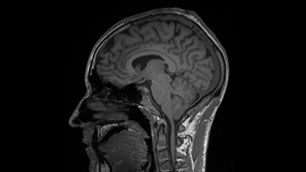

Hirne im Querschnitt

Schließlich ist der Tag für die Probanden mit dem Abstieg noch nicht beendet. Per Auto geht es für das erste MRT zur Bundeswehr in Fürstenfeldbruck. Um 19.30 Uhr wird das erste Probanden-Hirn im MRT 35 Minuten lang aufgenommen, um 3 Uhr nachts liegt mit dem Studienarzt der letzte im MRT, bevor in der Kaserne die erste kurze Nacht auf Meereshöhe beginnt.

Auch wenn erst die detaillierte Auswertung aller gesammelten Daten und Proben die Antwort darauf geben könnte, ob die Höhenkrankheit tatsächlich die Gefäßwände für Flüssigkeit und Eiweiß-Molekule durchlässig macht - schon der erste Blick auf die MRT-Aufnahmen und in die Studien-Tagebücher der Probanden ist vielversprechend. "Auf den Hirn-Aufnahmen zeigen sich bei zwei Probanden kleinere Ödeme, also Wassereinlagerungen - nicht gefährlich, weil sie so gering sind, dass sie nicht den gefährlichen erhöhten Hirndruck auslösen, aber deutlich sichtbar", sagt Studienarzt Ulrich Limper. Und bei den Tagebüchern zeigt sich ebenfalls eine Tendenz: Morgens waren die Symptome der Höhenkrankheit für die Probanden deutlich spürbarer - und dies passt wiederum zu der niedrigeren Sauerstoffsättigung im Blut am Morgen. Am Abend hingegen ging es vielen der Studienteilnehmer besser.

Am 5. September werden die Probanden allerdings noch einmal zur Blutabnahme gebeten. Nachdem ihr Körper wieder mehrere Tage lang "aufatmen" konnte, soll die Nachher-Werte zum Vergleich festgestellt werden. Mitte Dezember werden dann alle Probanden erneut im MRT untersucht - "wir wollen wissen, ob sich die Ödeme komplett zurückgebildet haben."